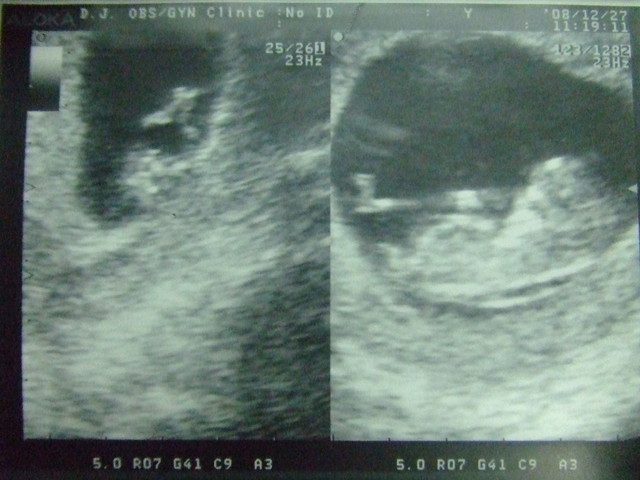

然後從超音波中見識到小寶貝的活力~

身體的跳動~

手腳的揮動~

現在的小寶貝已經是用臍帶來接收媽咪給妳的營養~

今天身長38.8mm~

但有點讓人擔心的是你的頸後透明帶有點寬~

下禮拜要去台大門診追蹤~